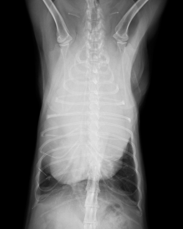

レントゲン検査にて、前胸部を大きく占める白い影が認められました。その部分を超音波にて確認したところ、心臓の前方に大きな腫瘤が確認できたので、針生検を行い、細胞診検査を行いました。br>

↑初回診察時の胸部レントゲン